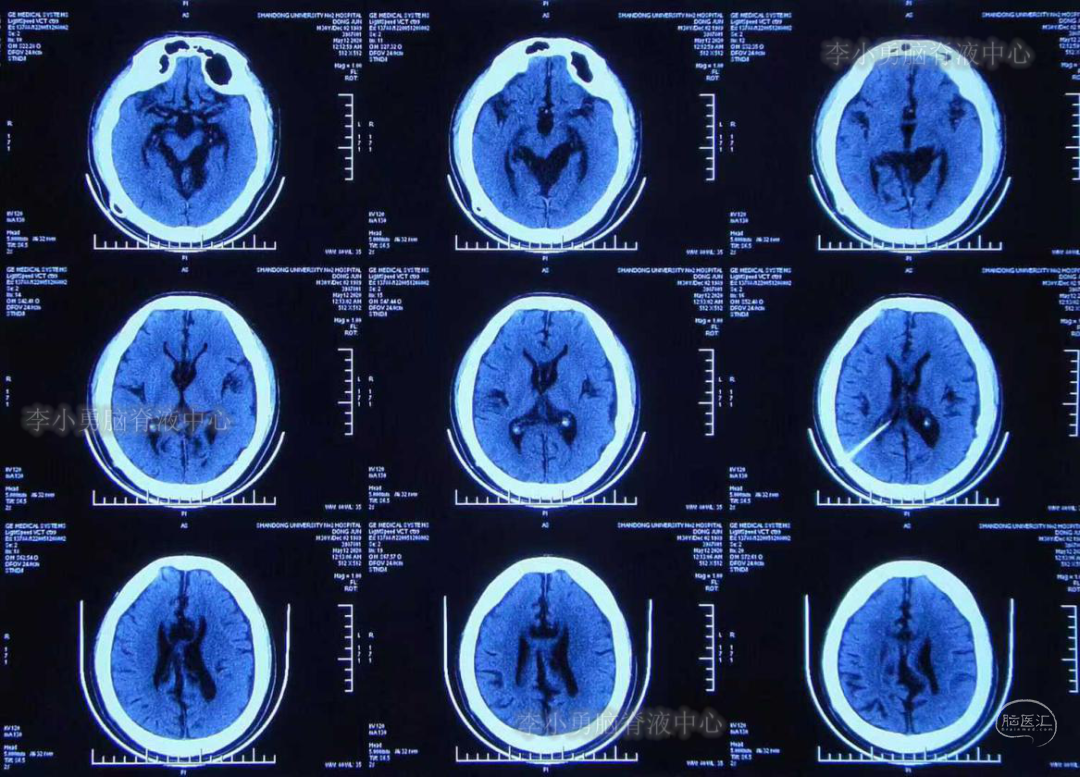

3年前(2017年,分流术后14年)患者再次出现头痛头晕,伴恶心呕吐。第3次就诊于山东省某三甲医院,行CT检查后(此片丢失),医生认为头部CT无异常,未进一步治疗,嘱患者回家观察。回家后患者头痛头晕仍间断出现,且出现越来越频繁,从开始的约半年出现一次头痛头晕到几乎每天都出现头痛头晕,且头痛程度越来越剧烈、无法忍受,于2020年5月11日(分流术后17年)第4次就诊于山东省某三甲医院住院,入院后行头部CT检查后,仍认为CT无异常(图-1)。

图-1:2020年5月12日头CT

给予患者行腰穿检查提示“颅压增高”,但具体“原因不详”,给予甘露醇降颅压治疗,但症状无好转。于2020年5月16日给予行头部MR检查:仍未见异常(图-2)。

图-2:2020年5月16日头部MR